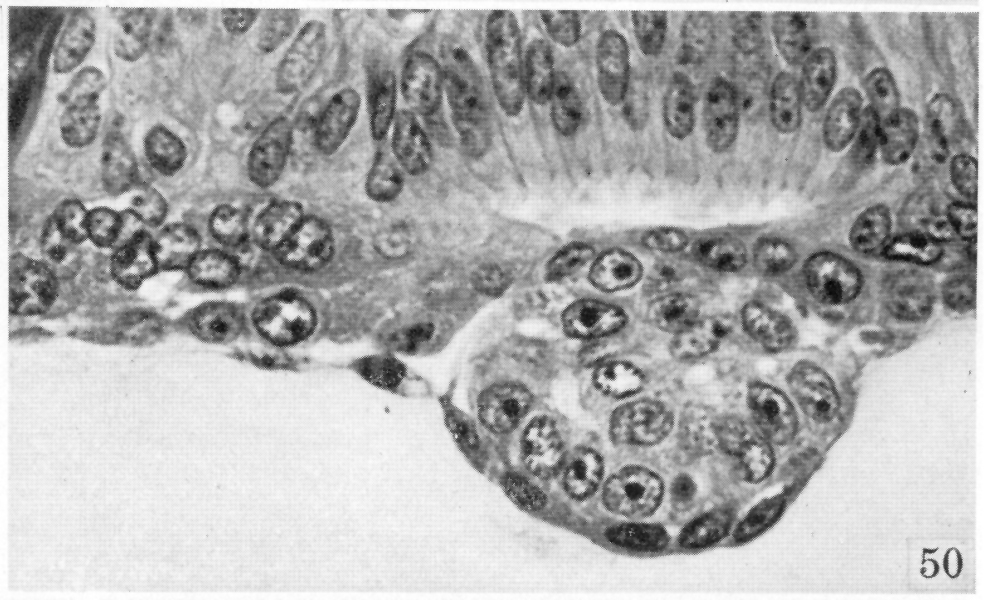

Fig. 50.

Heuser and Streeter, 1941